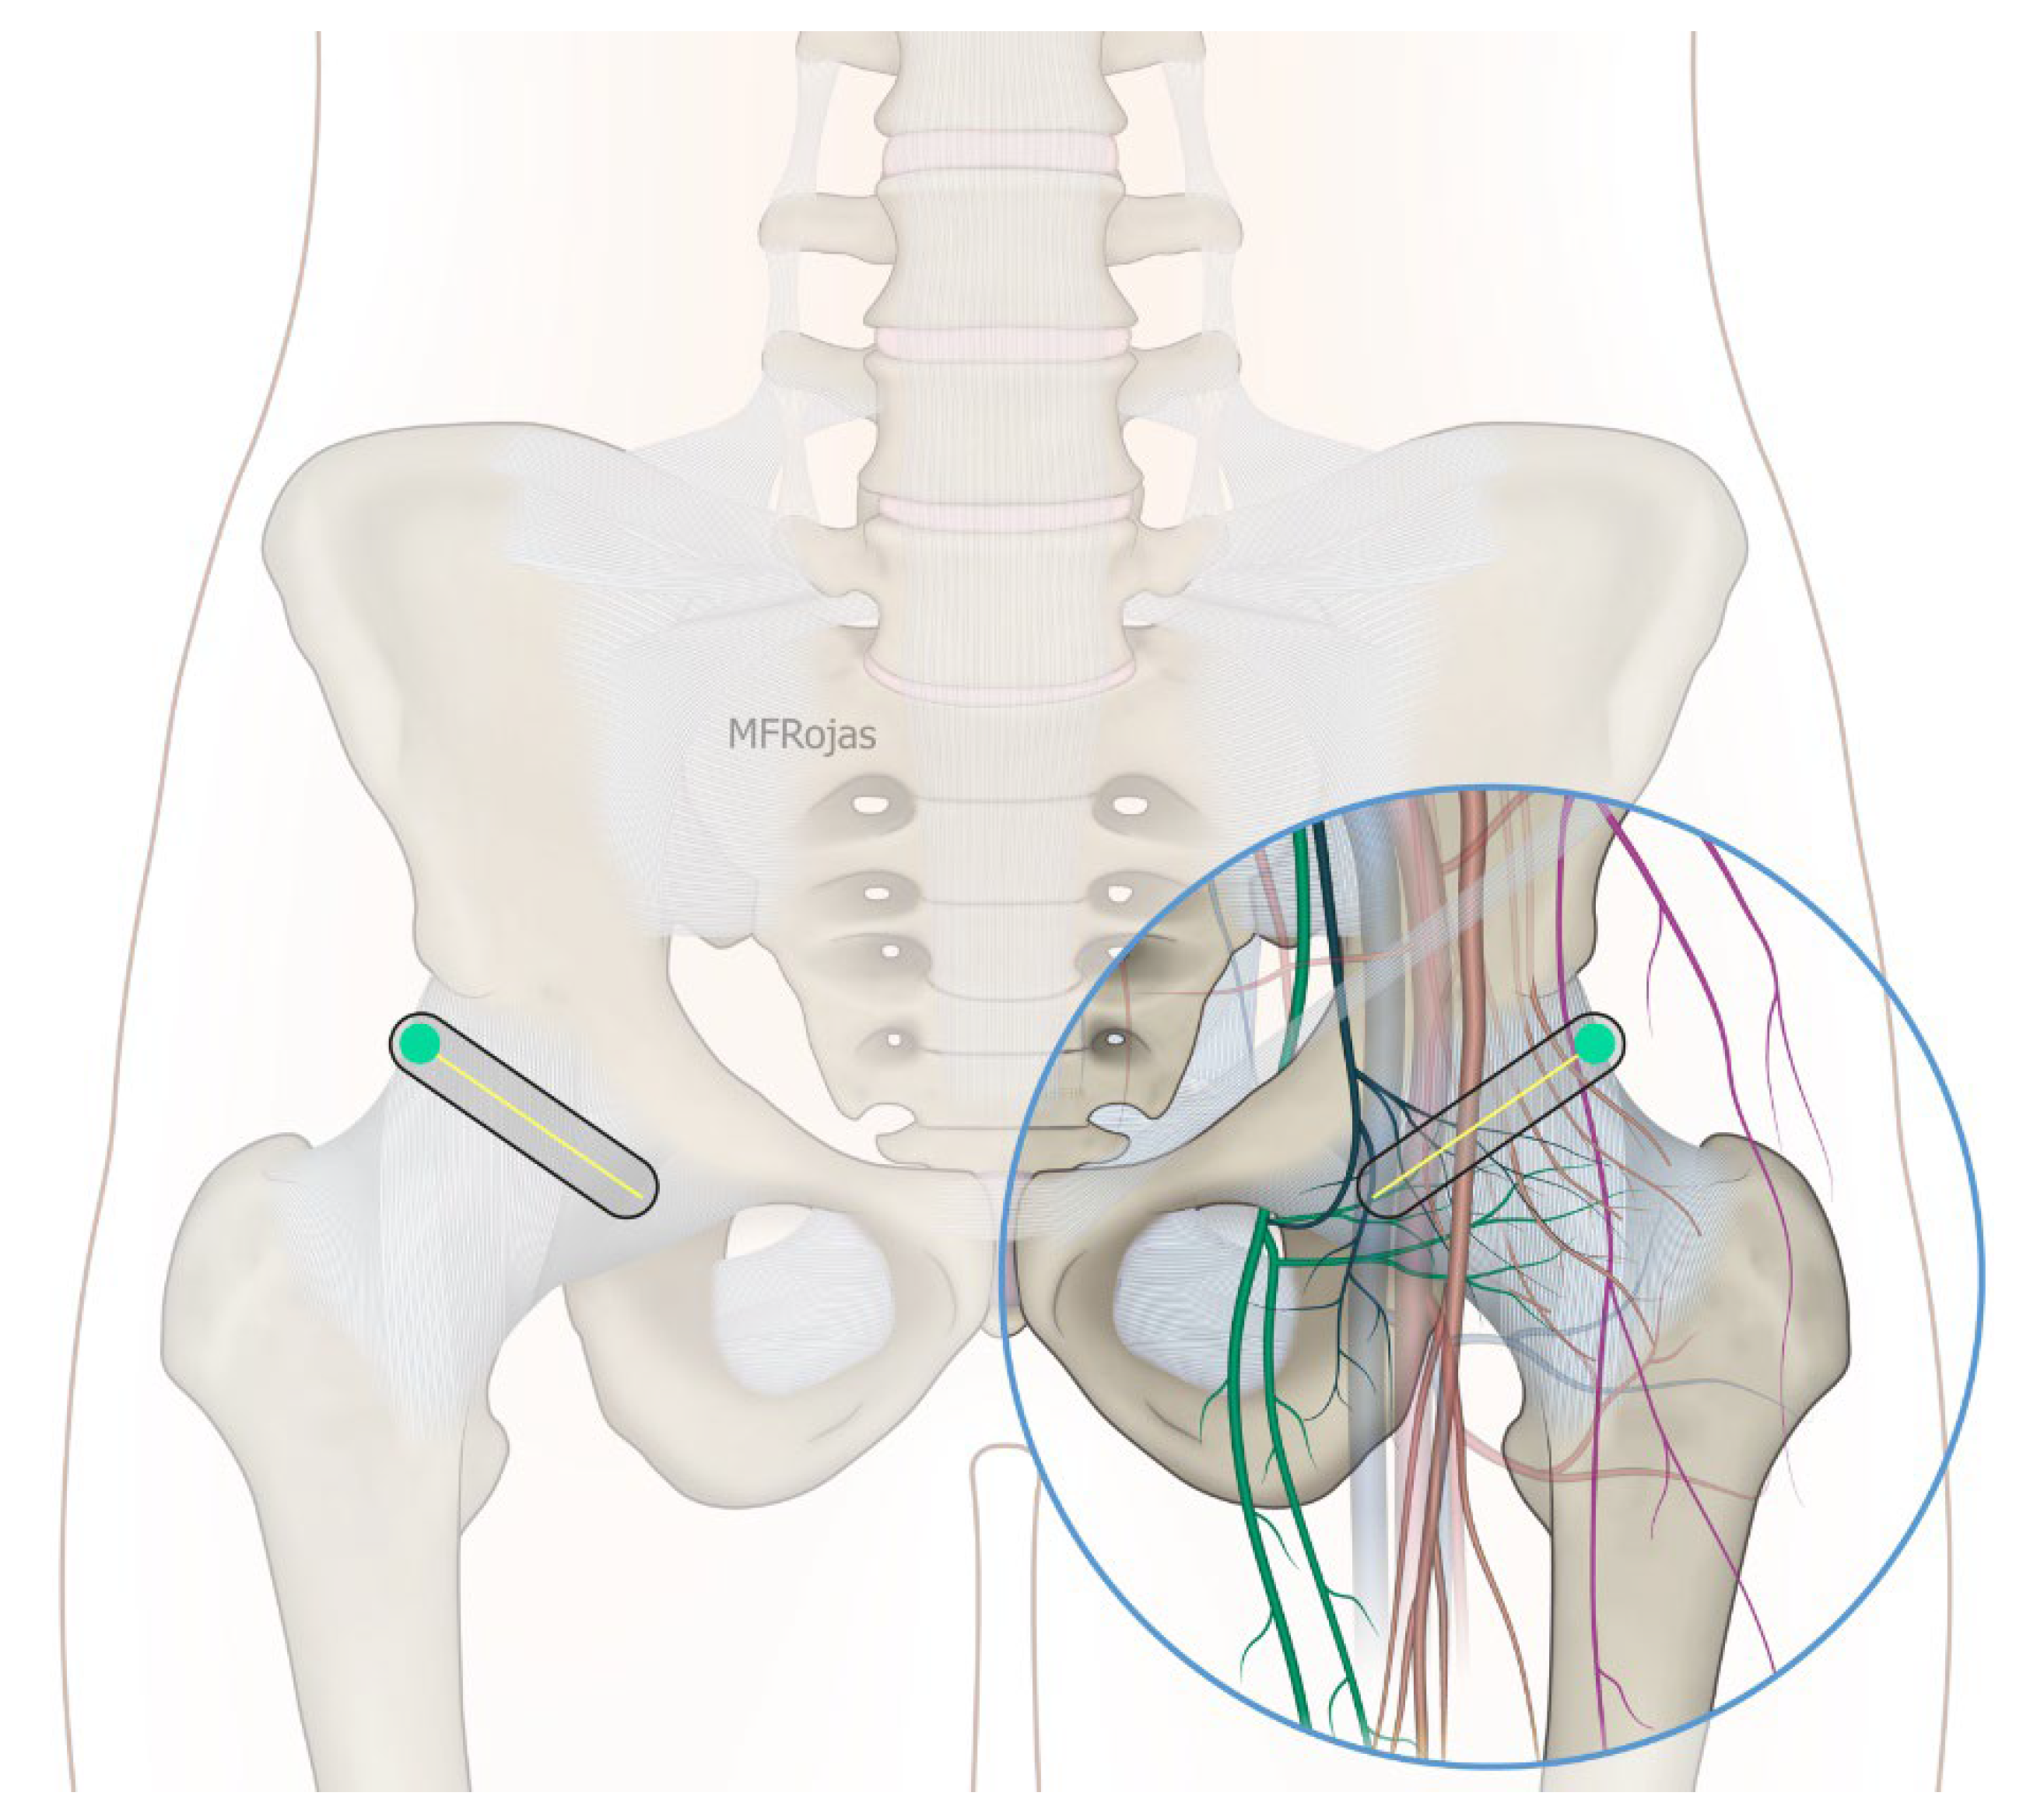

Figure 5. Ultrasound image showing the iliopsoas plane infiltration. FA: femoral artery, FH: femoral head, IP: iliopsoas, RF: rectus femoris, IFL: iliofemoral ligament; white arrow: needle.

In addition to the classical PENG injection, our modified approach highlighted the addition of pericapsular infiltration in the iliopsoas plane to cover the low articular branch of the femoral nerve and a sagittal approach to target the ONAB. The algorithm was still used to perform diagnostic blocks, followed by alcohol neurolysis 10 min later for those with a positive diagnostic block in the same setting under real-time ultrasound guidance (Philips Affiniti 70, 5–12 MHz linear probe or 1–5 Hz curved probe depending on the depth of the target). In the modified approach, the procedure consisted of 3 needle insertions with the use of 22-gauge 10 cm Quincke needles. The first needle for the high femoral nerve articular branches (high FNAB branches) and AON was inserted in the same way as the PENG approach between the anterior inferior iliac spine (AIIS) and the iliopubic eminence (IPE) deep to the psoas tendon (Figure 2 and Figure 3). A second needle for the low branches of FNAB was inserted in-plane from lateral to medial and advanced through the sartorius, rectus femoris and iliopsoas muscles. The final needle position was in the plane superficial to the iliofemoral ligament medial to the rectus femoris tendon over the femoral head (Figure 4 and Figure 5). The third injection for the obturator nerve articular branches was used to target the caudal aspect of the inferomedial acetabulum (IMA) by scanning in a sagittal plane with a caudal-to-cephalad needle trajectory. The precise localization of the caudal aspect of the IMA could be first approached via the ordinary way (an oblique scan) as described in our first case series [5]. The probe was slowly rotated obliquely until the acetabulum, femoral head, and neck were aligned in the same plane, with the superomedial acetabulum coming into view. The probe was then slid caudally with the end point being the presence of the acetabulum without the femoral head. This referred to the location of the inferomedial acetabulum. The probe was then adjusted until the IMA was in the middle of the image, followed by rotating the probe by approximately 60 degrees (Figure 6). In this scan, the pectineus, the caudal aspect of the IMA and, occasionally, the obturator externus were seen. The ONAB could be visualized in the wedge of the subpectineal space directly adjacent to the IMA. Before any needle insertion, the probe was tilted slightly medially towards the obturator foramen to look for the acetabular/posterior branch of the obturator vessels which are usually deeper than the ONAB. The needle was then inserted from caudal to cephalad in-plane until the needle tip reached the wedge space consisting of the ONAB (Figure 7). In case the wedge space could not be clearly visualized, the needle tip would then be advanced until touching the caudal bony surface of the IMA directly underneath the pectineus. Then, 0.5–1% ropivacaine (4, 3 and 2 mL, respectively) was injected into the above three landmarks. The needles were left in situ during the diagnostic test while their positions were reconfirmed by ultrasound before 100% alcohol was injected into the above targets with volumes in a 1:1 ratio between alcohol and local anaesthetics. A decrease of ≥50% in composite pain score on hip flexion at 45 degrees 10 min after the blocks signified a positive diagnostic block. As a post-neurolysis routine manner, stylets were reinserted before needle withdrawal.